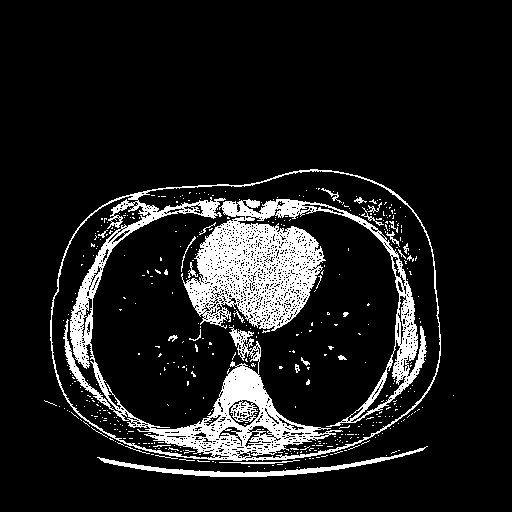

Original VENOUS CT scan

Full window (WL 1023.5, WW 4095 β†’ Low βˆ’1024, High +3071)

Actual HU range: [-1024.0, 3071.0]